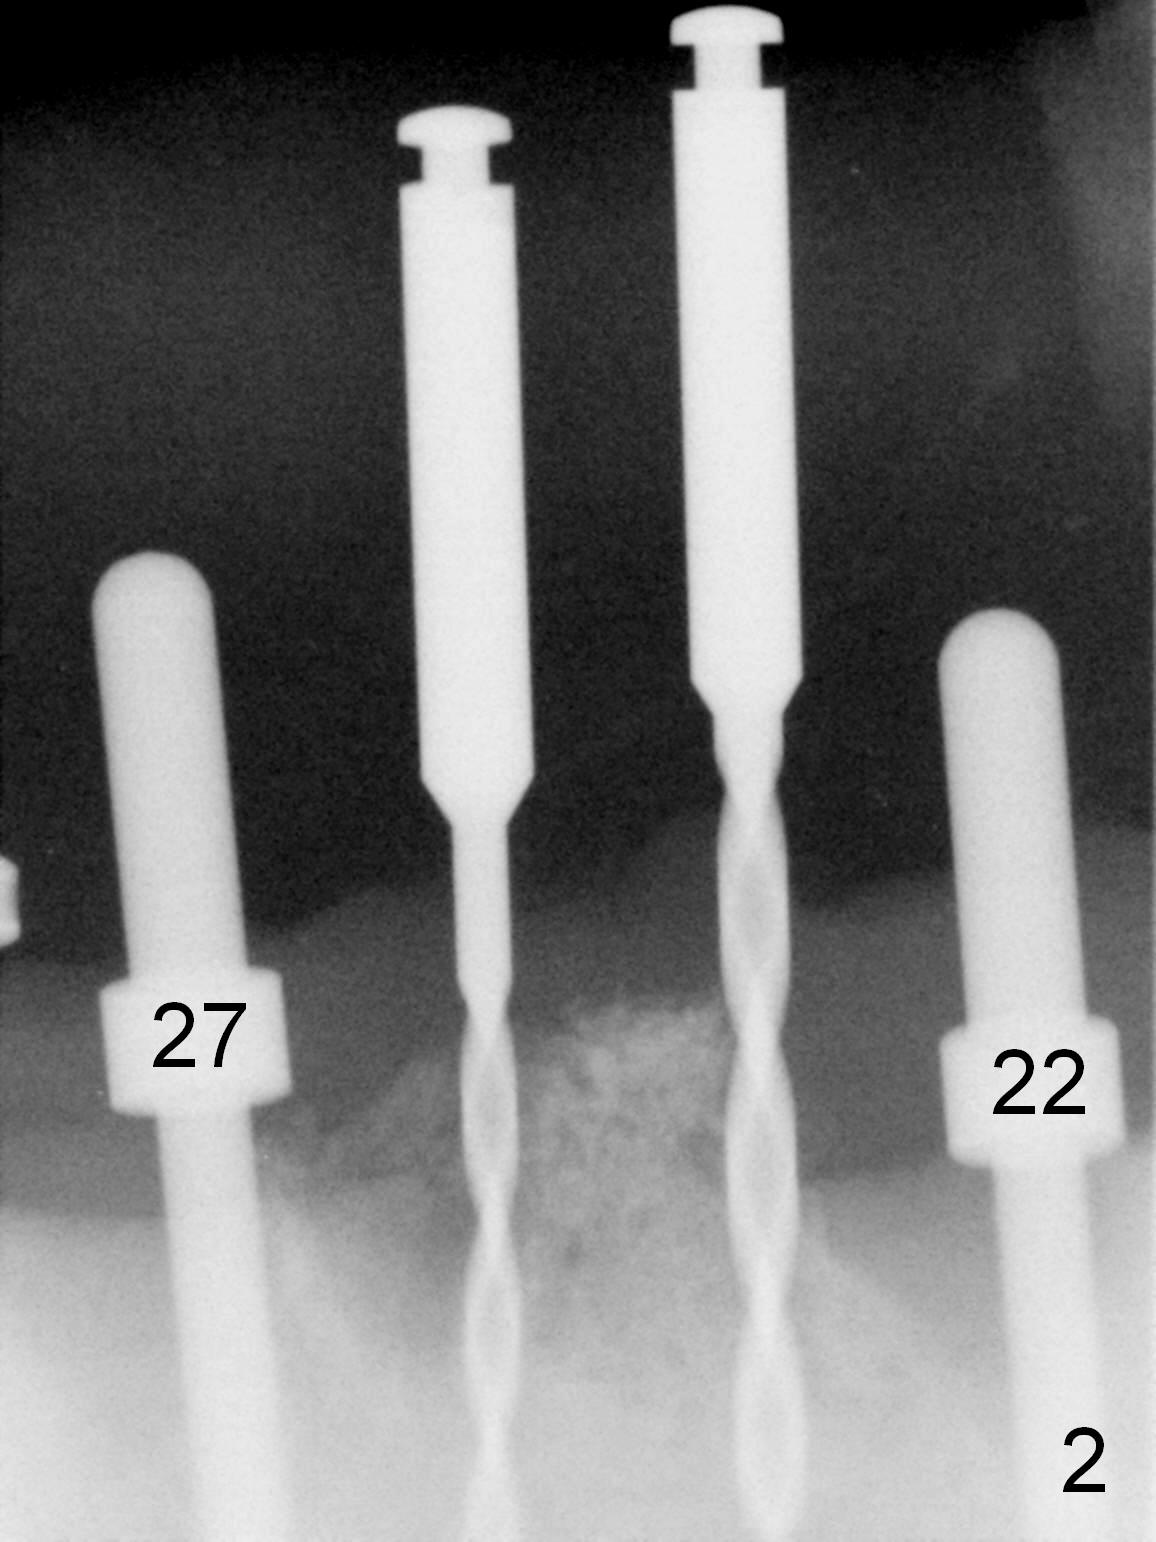

As expected, the bone density in the mandibular anterior region is found to be high during initial osteotomy (Fig.1-3). Five implants are placed at the sites between #22 and 28 (Fig.4,5): 3x14(2) mm 1-piece (bone-level) implants in the incisor region; 4.5x17 mm 2-piece (tissue-level) ones in the canine/premolar area. All of the implants are placed as lingual as possible. Bone graft is placed (*). Red dashed line: the superior border of the Inferior Alveolar Canal. Immediate splinted provisional bridge is fabricated. One week postop, periodontal dressing remains attached to the provisional and the gingiva.

The implants remain asymptomatic years months post cementation (Fig.12), while the one at #27 is associated with buccal and lingual swelling and hemorrhage and bone loss (Fig.13). There is bone loss distal to #27 without symptom 3 years 9 months post cementation (Fig.12). Periimplantitis develops buccal and lingual 4 years 5 months post cementation (coronavirus, Fig.13). Sticky bone and PRF are used after debridement. There is no discomfort 7 days postop (Fig.14,15).